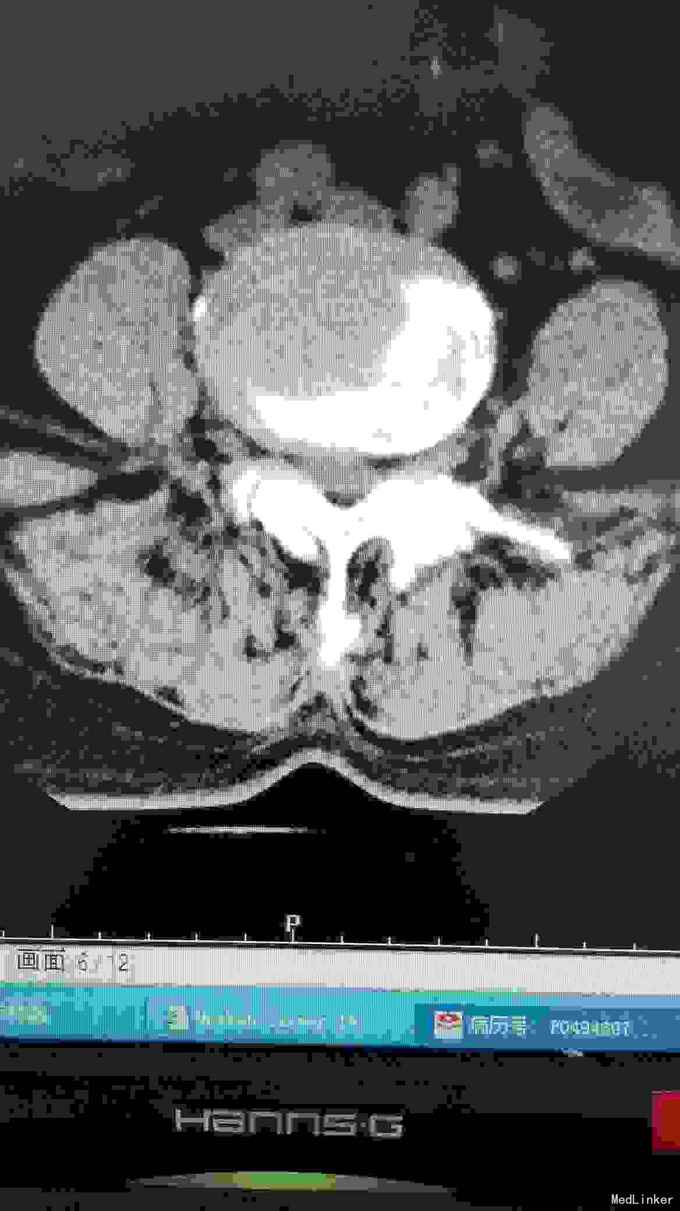

腰椎影像检查提示椎间盘突出,椎管狭窄,退变侧弯。

诊断腰椎间盘突出症,腰椎管狭窄症,腰椎退变性侧弯。 在全麻下行腰椎固定,减压,畸形矫正融合术。